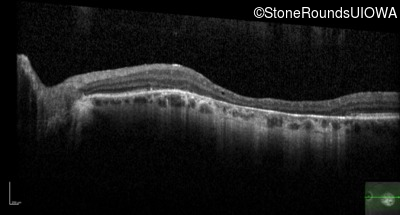

Optical Coherence Tomography - Right - 20/50 -1

Exemplar / OCT Stack